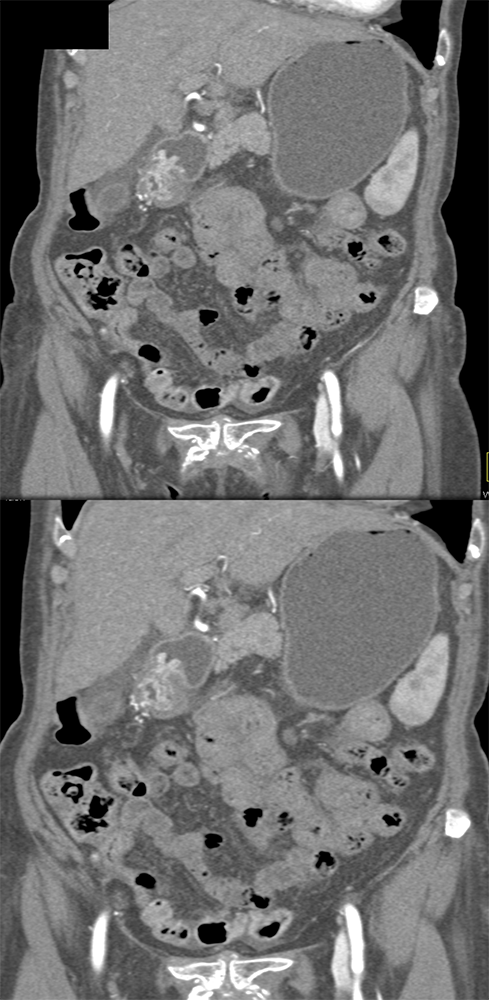

Watermelon stomach (WMS), or gastric antral vascular ectasia (GAVE) ![]() |

“In our patient, the findings of prominent mucosal folds extending from the pylonic channel on upper gastrointestinal series and the thickened antral wall on CT scans correlate well with the known pathologic appearance of gastnic antral vascular ectasia. Histologically, antral thickening results from a combination of foveolar and fibromuscular hyperplasia. Grossly, the antral fold prominence appears to result from bunching of the mucosa in the thickened, hypercontractile antrum.” Gastric antral vascular ectasia ("watermelon stomach"): radiologic findings. Urban BA, Jones B, Fishman EK, Kern SE, Ravich WJ. Radiology. 1991 Feb;178(2):517-8. |

“Gastric antral vascular ectasia primanily affects women (9:1 female-to-male ratio) aged 56-76 years, and is associated with liver cirrhosis (37%) and achlorhydnia (35%). The usual symptoms are iron-deficiency anemia and melena due to chronic gastrointestinal bleeding from the dilated, superficial, and easily traumatized vessels. Antrectomy is curative, but endoscopic treatment with heat probes or lasers has shown promise.” Gastric antral vascular ectasia ("watermelon stomach"): radiologic findings. Urban BA, Jones B, Fishman EK, Kern SE, Ravich WJ. Radiology. 1991 Feb;178(2):517-8. |